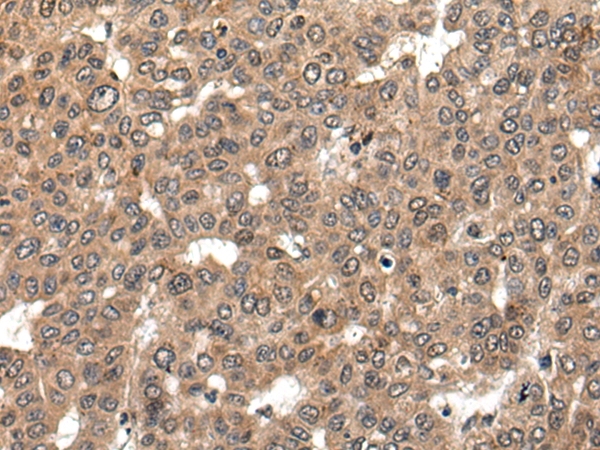

The image on the left is immunohistochemistry of paraffin-embedded Human liver cancer tissue using 46595(L1RE1 Antibody) at dilution 1/20, on the right is treated with synthetic peptide. (Original magnification: x200)